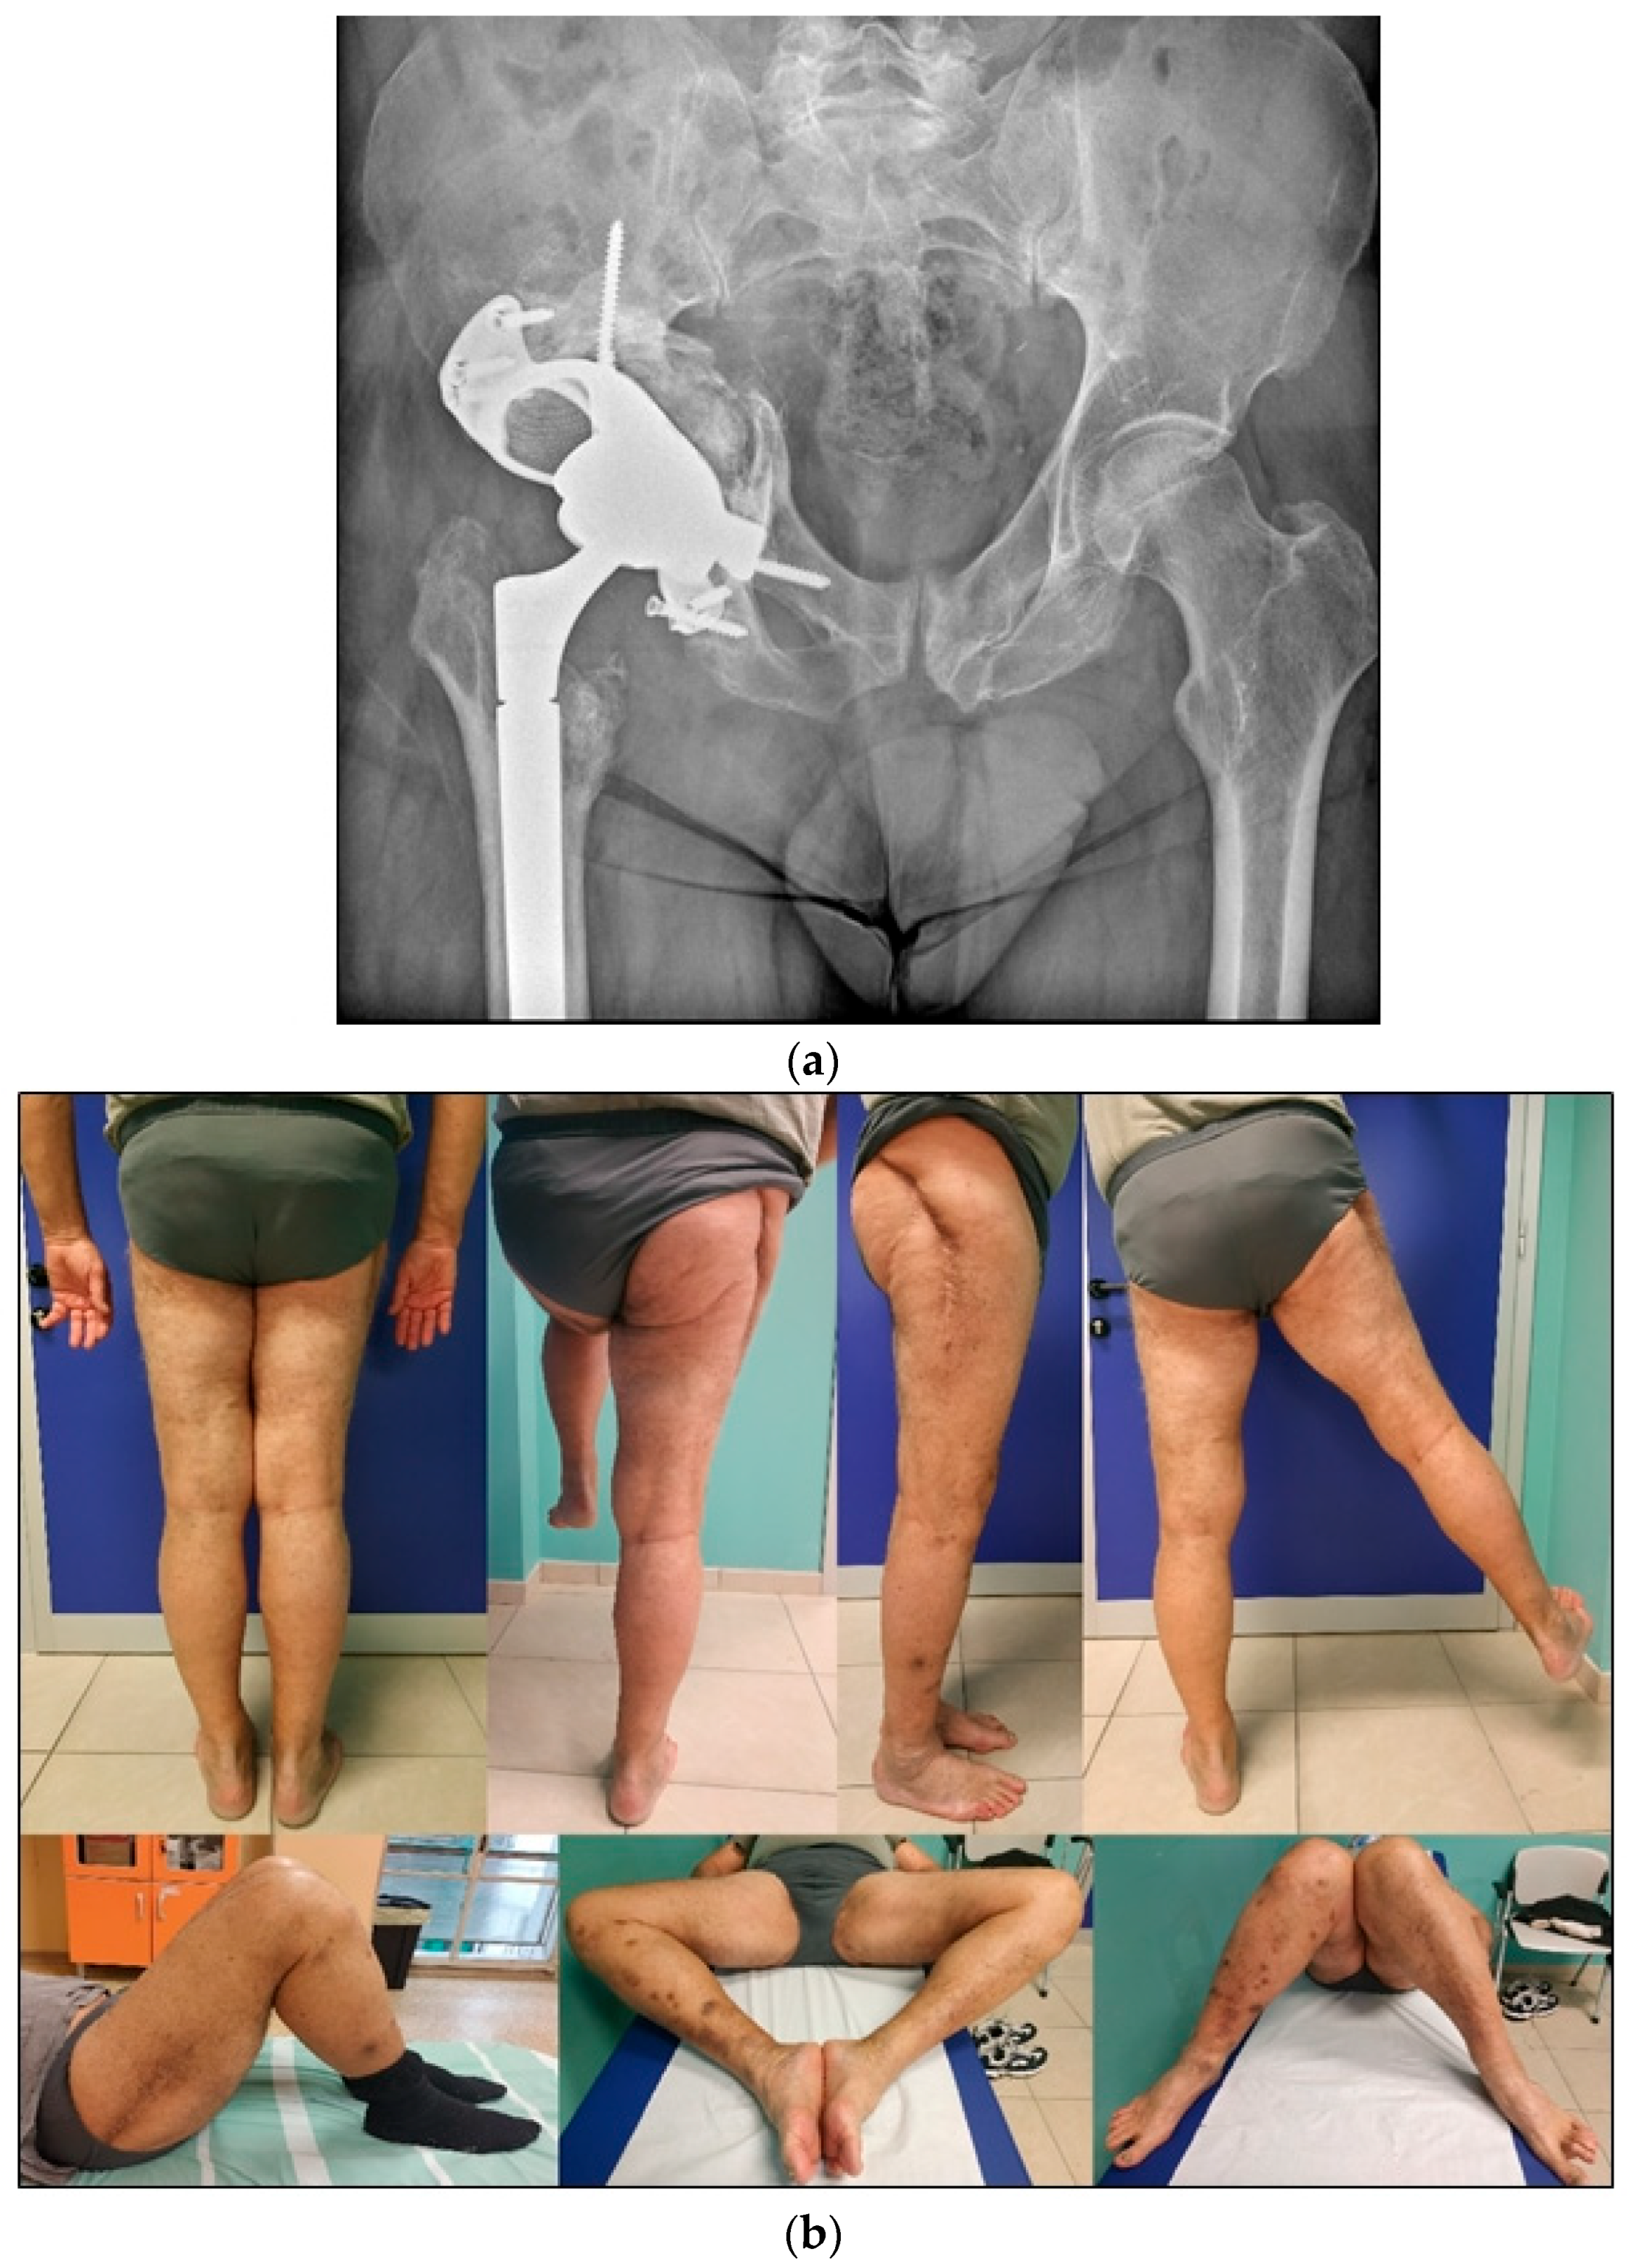

4.3. Acute THA in Acetabular Fractures

5. Conclusions